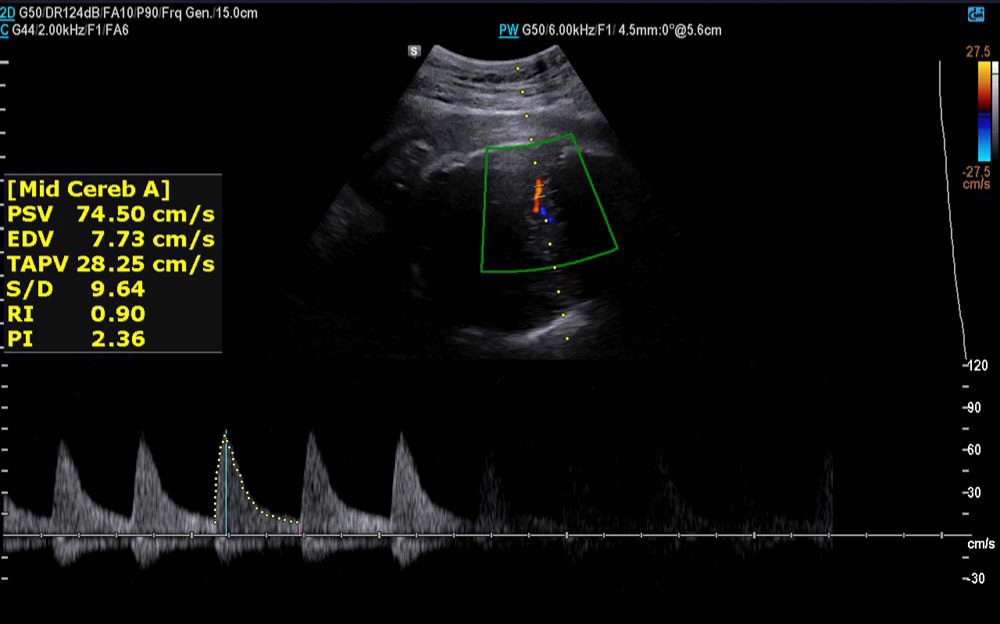

✅️✅️✅️تفسیر سونو داپلر۳۶ هفته🙏🏻

خداروشکر شواهد رشدی بهتر شده و در سونوگرافی شواهدی به نفع محدودیت رشد داخل رحمی و همچنین کمبود اکسیژن جنین وجود ندارد ولی مقداری مقاومت شریانی دارید به پزشکتان حتما مراجعه کنید تا درمورد زایمان و یا شروع انوکساپارین تصمیم گیری شود

جانم pi 2.4 ولی تحت نظر باشید مشکلی ندارد